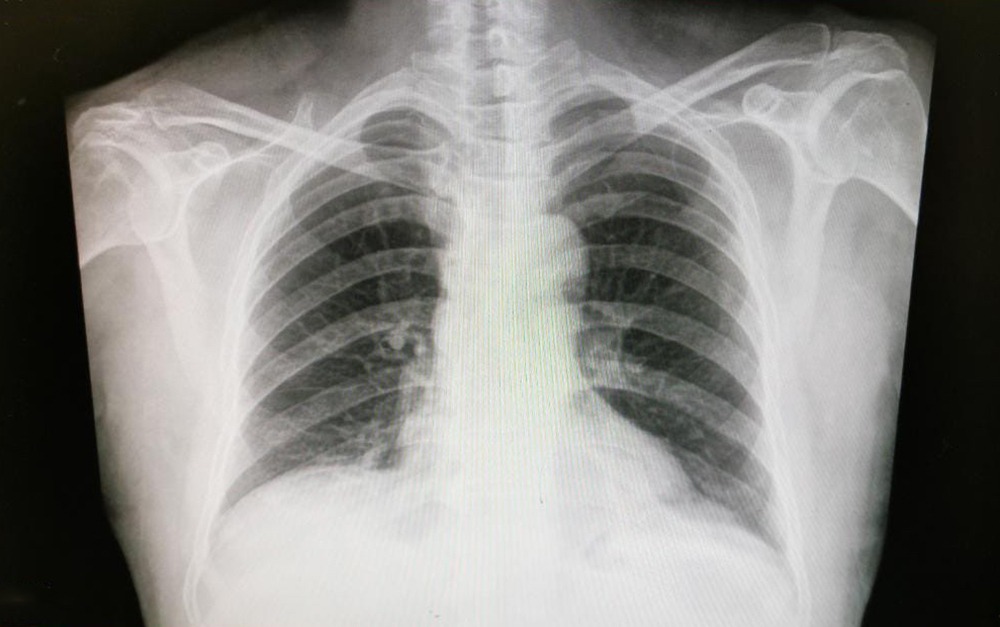

Ciudad de México- El Instituto de Seguridad y Servicios Sociales de los Trabajadores del Estado (ISSSTE), a través del Centro Médico Nacional (CMN) “20 de Noviembre”, cuenta con innovadores tratamientos que han permitido controlar mejor algunas variantes del cáncer de pulmón y aumentar la sobrevida de pacientes hasta en cuatro años.

En el marco del Día Nacional del Cáncer de Pulmón, el médico oncólogo, Fernando Aldaco Sarvide, subrayó que esta enfermedad causa la muerte de una de cada 10 personas que fallece por tumores malignos en México.

El cáncer de pulmón no es de los más prevalentes, pero sí es de las enfermedades oncológicas con la mortalidad más alta, junto a neoplasias (tumores), sarcomas (tipo de cáncer que se origina en tejidos) y melanoma (cáncer de piel que surge cuando las células comienzan a crecer sin control).